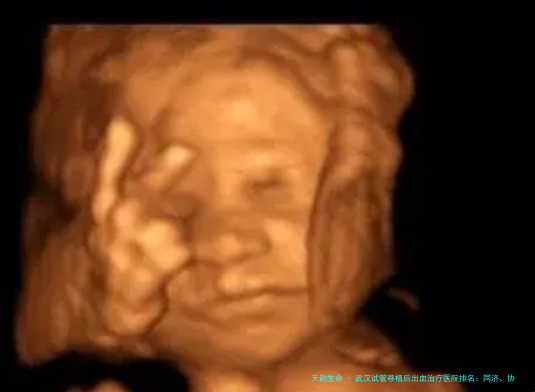

在辅助生育技术期间,胚胎移植后出现少量出血是很多准妈妈会碰见的状况。这既可能是着床期的正常反应,亦可能是需要及时干涉的信号。选定一家处理有经验、技术成熟的医院极为重要。即日,我们就来详细了解一下武汉地区在处置移植后出血方向备受信任的试管医院,并附上本地优良生殖医学中心的深度介绍.

以上即是“武汉试管移植后出血治疗医院排行:同济、协和、省妇幼等三甲医院专科解析及本地优质机构精选”,这一些医生均来自规范医院,享有丰富临床经验和精湛技术,信誉经得起市场检验。想察看医生图片案例、网络上面诊、了解医生,咨询本站客服,获得一双一专用客服沟通服务!